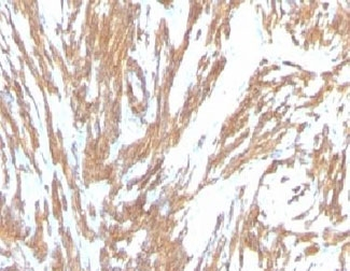

Immunofluorescent staining of fixed human HeLa cells with Smooth Muscle Actin antibody (clone SPM332, green) and NucSpot nuclear stain (red).

IHC: Formalin-fixed, paraffin-embedded Leiomyosarcoma stained with Smooth Muscle Actin antibody (clone SPM332).